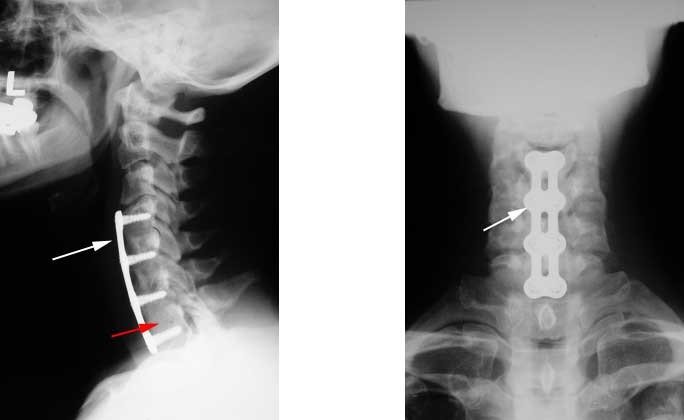

After placement of a graft in the disc space, a metallic plate is placed to lock the vertebrae and the bone graft. The plate helps increase the success of the fusion surgery.

Below, the red arrow point to bony plugs placed in between the vertebrae. The titanium plate is marked with the white arrows.